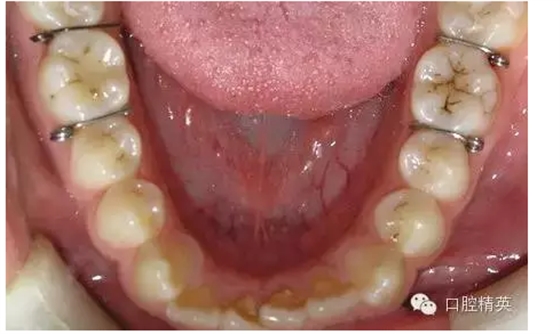

圖2

◆分牙簧各個口腔醫(yī)療器材商都有成品供應,但基本上是圖1形狀,即未激活狀態(tài),正確的使用方法是:在操作前用細絲鉗夾住簧圈處齦臂向內彎折,使齦臂末端靠近合臂,形成角度(圖2),分牙時撐開,插入鄰牙間,利用兩臂的剪切彈力,產生間隙。